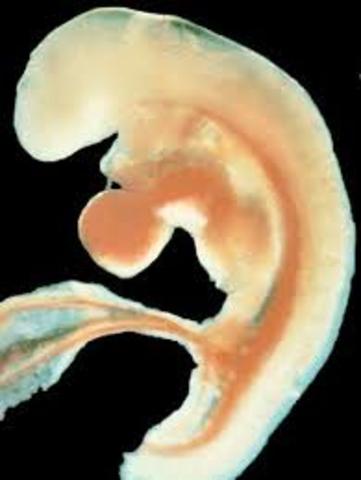

En esta semana, se pude observar el tubo neural, bordeado por somitas, de donde surgirán la columna vertebral y las costillas. El corazón empieza a latir, aunque sus cavidades no están totalmente desarrolladas.